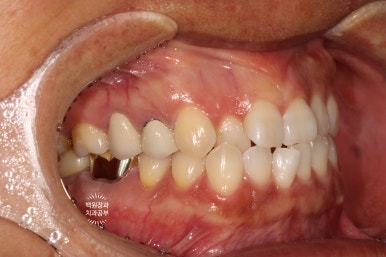

잘 보시면, 처음에 치료된 모습 그대로 잘 유지되고 있는 임플란트 크라운을 왼쪽에서 보실 수 있습니다.

충분히 단단한 지르코니아 크라운으로 제작된 임플란트는 오랜 수명을 자랑합니다!

그리고 오른쪽 사진에서, 아주 완벽하게 잘 유지되고 주변 잇몸과 조화로움을 자랑하는 임플란트를 보실 수 있을거에요. 얼핏 보면 자기 치아랑 헷갈릴 정도라니깐요..

오스템임플란트와 덴티움 뼈이식재 조합이 아주 좋은 결과를 보여주었네요.